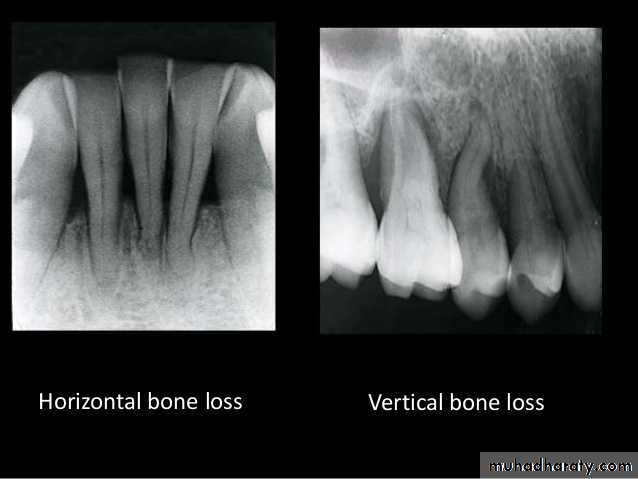

Direction :

Intercrestal bone should be parallel with line dawn from the CEJ of one tooth to that of the contacting tooth.

1. Horizontal bone loss:- When loss occurs on a plane that is parallel with a line drown.

2.Vertical bone loss:- when there is greater bone loss in one tooth than on the adjacent tooth, so the bone level is not parallel with a line joining the CEJ.